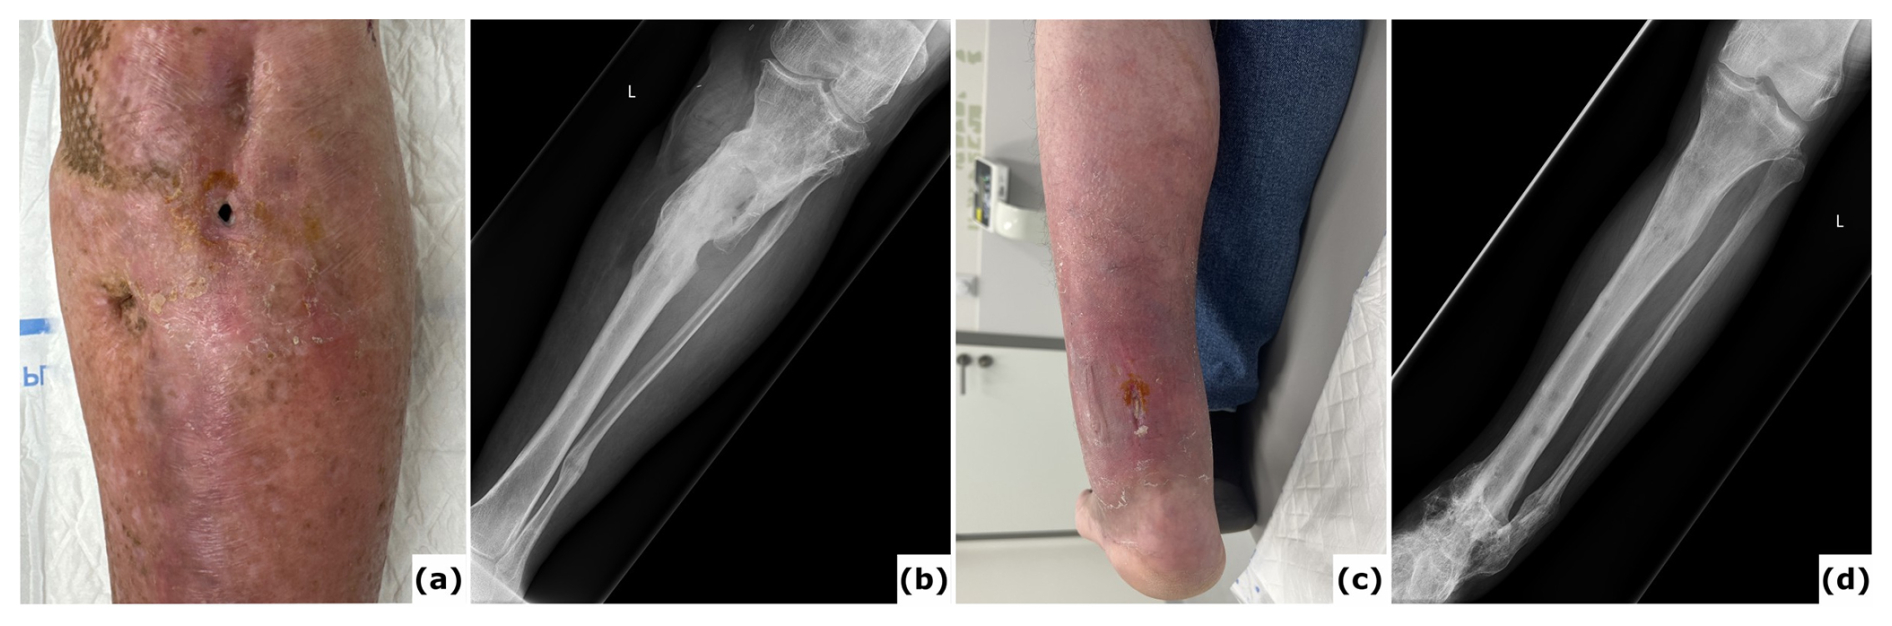

Figure 4Chronic infection (osteomyelitis) following extended external fixation. (a) Clinical image presenting a fistula with purulent fluid drainage in a 64-year-old patient after multiple surgical procedures for fracture-related infection (FRI) of the proximal tibia with non-union. (b) Anteroposterior radiograph of the tibia showing consolidation of the proximal tibia fracture; the external fixation time (EFT) was 16 months. (c) Clinical image depicting a chronic wound on the posterior aspect of the ankle in a 54-year-old patient after several surgical interventions for FRI of the distal tibia. Bone transport was performed as treatment, with an EFT of 12 months. At referral, the patient had local and systemic signs of infection and was prescribed oral antibiotics. These episodes have recurred intermittently over 3 years following removal of the external fixator. (d) Anteroposterior radiograph of the tibia demonstrating consolidation at all sites.